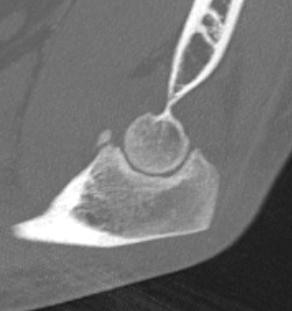

Overstuffing

| Lesser sigmoid notch | Symmetry of ulnohumeral joint |

|---|---|

|

Radial head shoulder articulate with lesser notch

Ensure no gapping of lateral ulnohumeral joint |

![]() |

- cadaveric study

- increased medial ulno-humeral joint line gapping with overlengthening of 6 or 8 mm

- increased lateral ulno-humeral joint line gapping with overlengthening of 2 mm